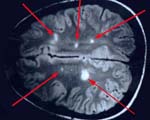

Лабораторні та інструментальні методи діагностики використовують для виявлення субклінічних вогнищ ураження, а також для оцінки активності патологічного процесу. Основним методом, що підтверджує діагноз «розсіяний склероз», є МРТ головного мозку , Яка дозволяє виявити наявність і топографічний розподіл передбачуваних вогнищ демієлінізації.

МРТ головного мозку. Множинні гіперінтенсивні осередки в глибокому білій речовині (демієлінізуюче поразки)